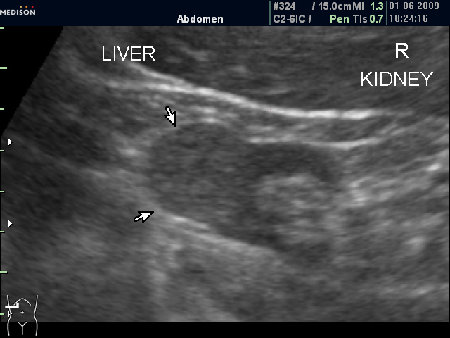

Женщина 72 лет. При УЗИ выявлены два аваскулярные образования: в нижнем полюсе правой почки и у верхнего полюса почки.

Уникальность случая в том, что эти изменения - БЕЗ ДИНАМИКИ с 2005 года.

Опухоль почки?

Без допплера явно опухоль почки